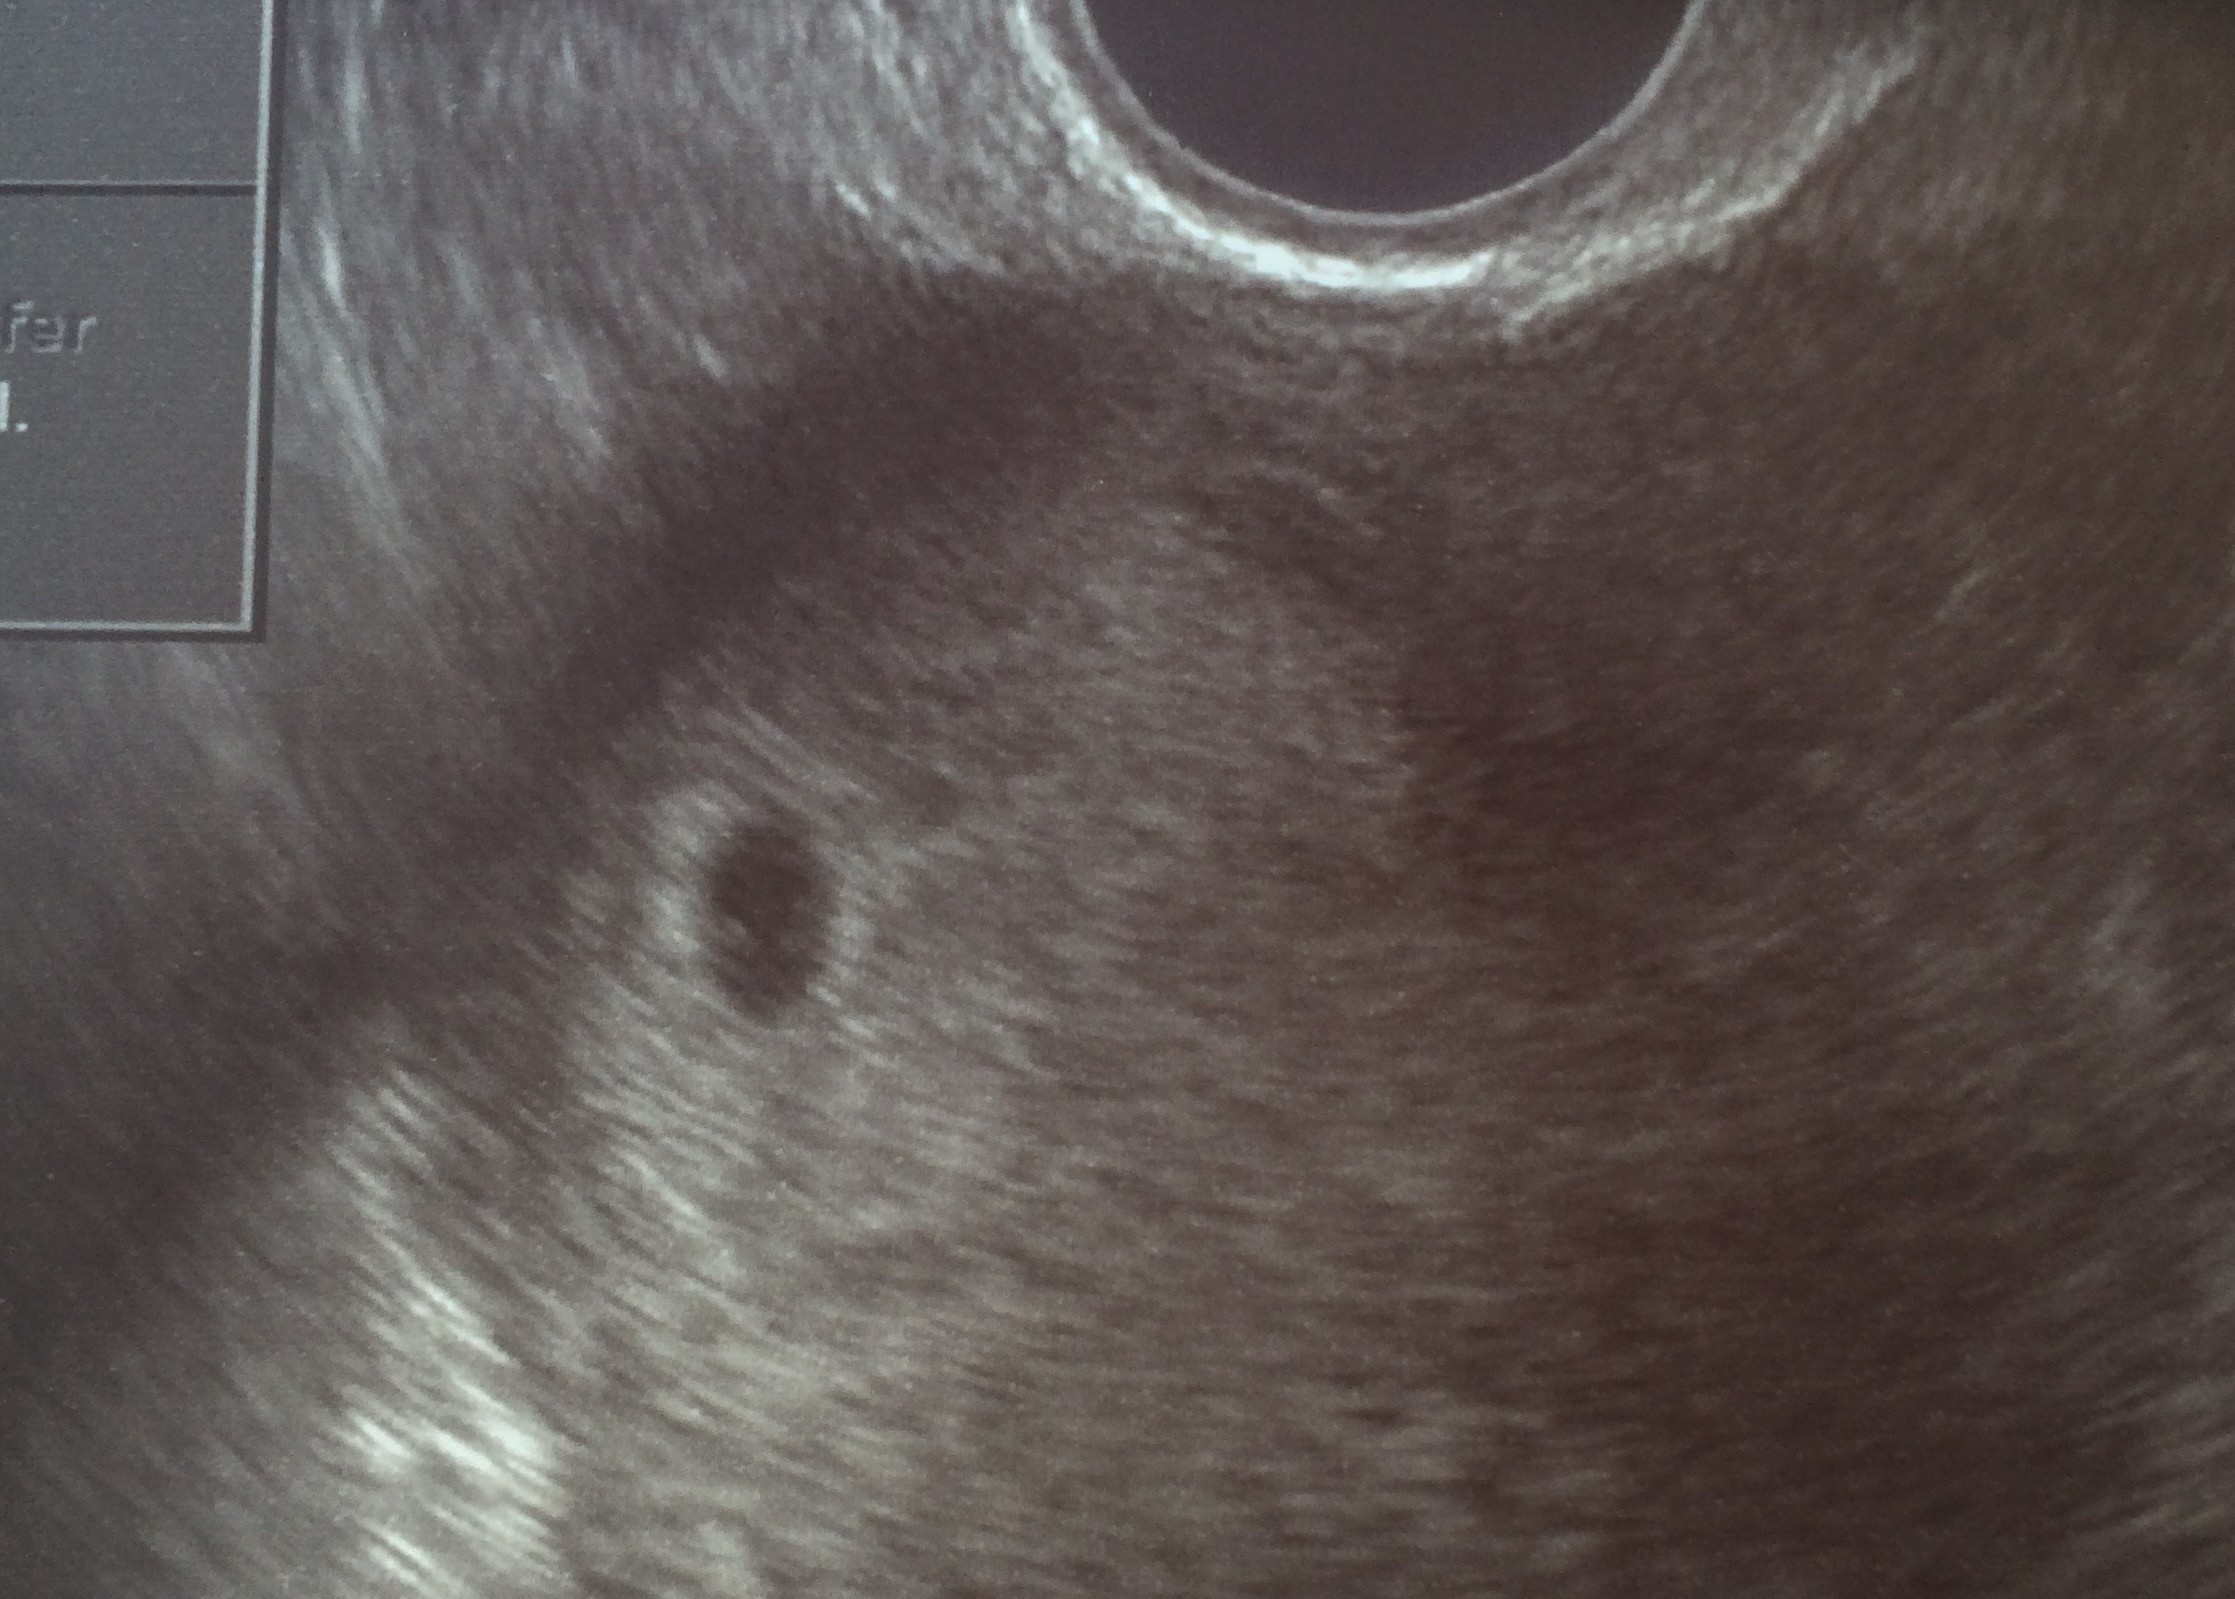

image.jpeg

• image.jpeg

554 KB · Wyświetleń: 344